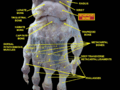

Scaphoid shown in yellow. Left hand. Dorsal surface. Cross section of wrist (thumb on left). Scaphoid (labelled as "Navicular") shown in red.

Cross section of wrist (thumb on left). Scaphoid (labelled as "Navicular") shown in red. Wrist joint. Deep dissection. Posterior view.

Wrist joint. Deep dissection. Posterior view. Scaphoid forms the radial (thumb-side) border of the carpal tunnel. Wrist joint. Deep dissection. Anterior (palmar) view.

Scaphoid forms the radial (thumb-side) border of the carpal tunnel. Wrist joint. Deep dissection. Anterior (palmar) view.